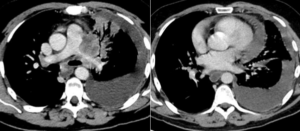

C

Masa pulmonar izquierda que afecta al bronquio izquierdo y estrecha la arteria pulmonar. Colección pleural y pericárdica.

D

Masa pulmonar izquierda que afecta al bronquio izquierdo y estrecha la arteria pulmonar. Colección pleural sin afectación pericárdica.